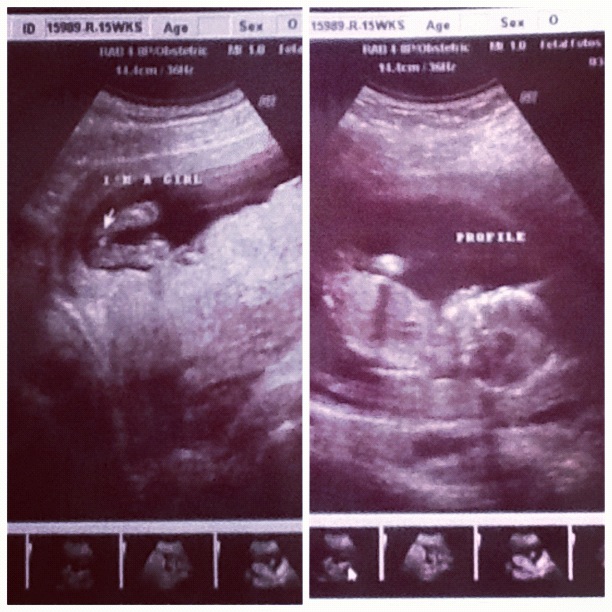

it's a.....

Last week we found out these sweet little guys are going to have a little sister. Yep... it's a GIRL!!!! We were pretty dang surprised and I still can't quite wrap my head around it but we are super excited!